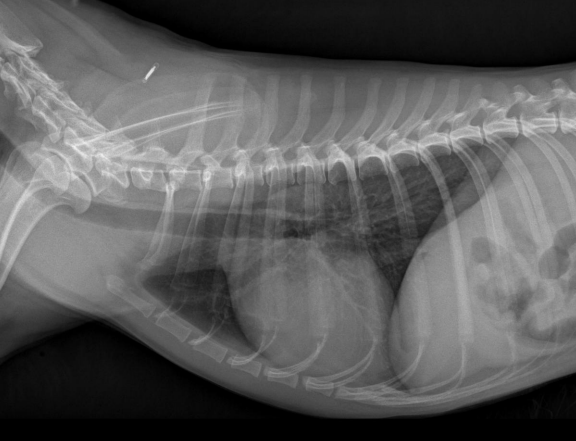

Radiografia laterolateral

Dependiendo de la posición los gases van a un lado o a otro: Decúbito lateral derecho Radiografía Lateral

- Gas en fundus

- Se ve mejor cola del bazo

- Mayor separación de siluetas renales

Decúbito lateral izquierdo

- Gas en píloro

- Mejor visualización delduodeno

La Y del diafragma es en laterolateral izquierda, en la laterolateral derecha se ven lineas mas paralelas.